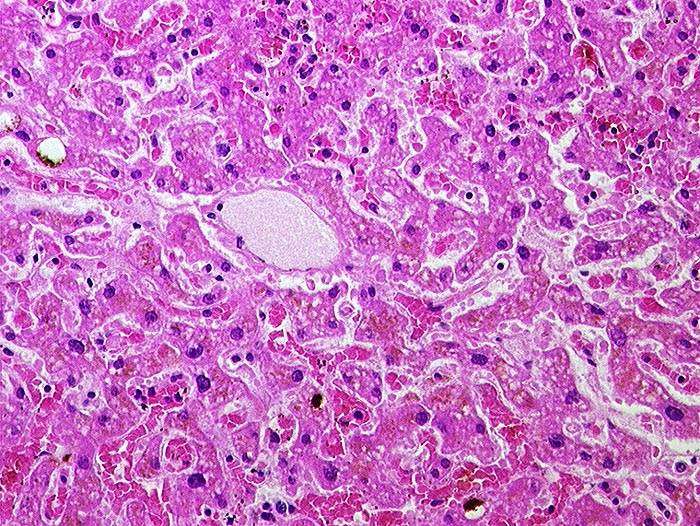

PathoPic – image database / PathoPic ID 1059 - Subakute Stauung

Subakute Stauung

vaskulär / Durchblutungsstörung

Leber

In der Mitte eine Zentralvene. Die angrenzenden Sinusoide sind deutlich erweitert und prall gefüllt mit Erythrozyten. Die Leberzellbalken sind leicht verschmälert (Druckatrophie). Die perivenösen Hepatozyten enthalten teilweise braunes Lipofuscinpigment.

In der Bindegewebsfärbung kein vermehrter Fasernachweis rund um die Zentralvene.